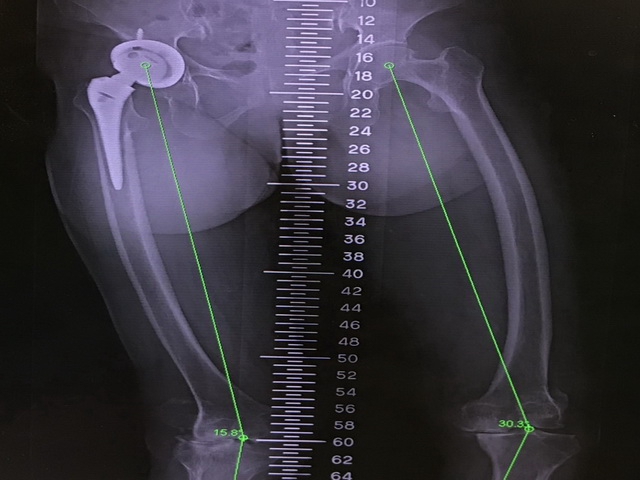

大里仁愛醫院黃贊文部長分享,李阿嬤的雙腳膝蓋變形很少見,在醫學上稱之爲風吹式變形(windswept deformity)。這種變形指的是一側膝關節外翻(X型腿);而另一側是膝關節內翻(O型腿),看起來好像是被風吹歪的樹一樣變成「 》」型。原本關節炎造成疼痛再加上重心歪了一邊,所以走路時常容易跌倒。在這種風吹式變形的初期,可以藉由截骨矯正的保膝手術將雙腳的變形由「 》」矯正成「 ||」讓膝關節平均受力,走路時重心才會穩定,可以減少將來要接受人工膝關節置換手術的風險。

黃醫師指出,李阿嬤的風吹式變形的手術難度很高,右膝關節的膝外翻變形大於15度且左膝關節的膝內翻變形大於30度。不論是右膝還是左膝,這種大角度的變形都是屬於相當困難的人工膝關節置換手術,幾位醫師看了X光後都紛紛打了退堂鼓,所以才輾轉到大里仁愛醫院來安排手術。